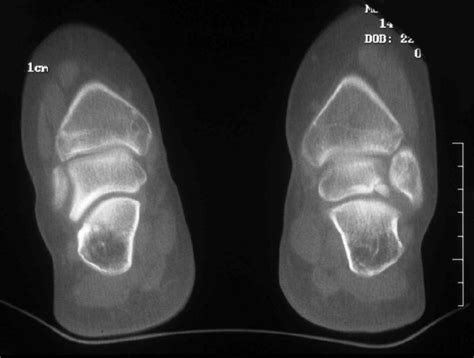

• Imaging Tests: Imaging tests, such as X-rays, MRI, or CT scans, are used to visualize the bone and cartilage within the ankle joint. These tests can help identify the location and extent of the lesion.

Imaging tests are particularly important in diagnosing Osteochondritis Dissecans Ankle, as they can provide detailed information about the condition of the bone and cartilage.